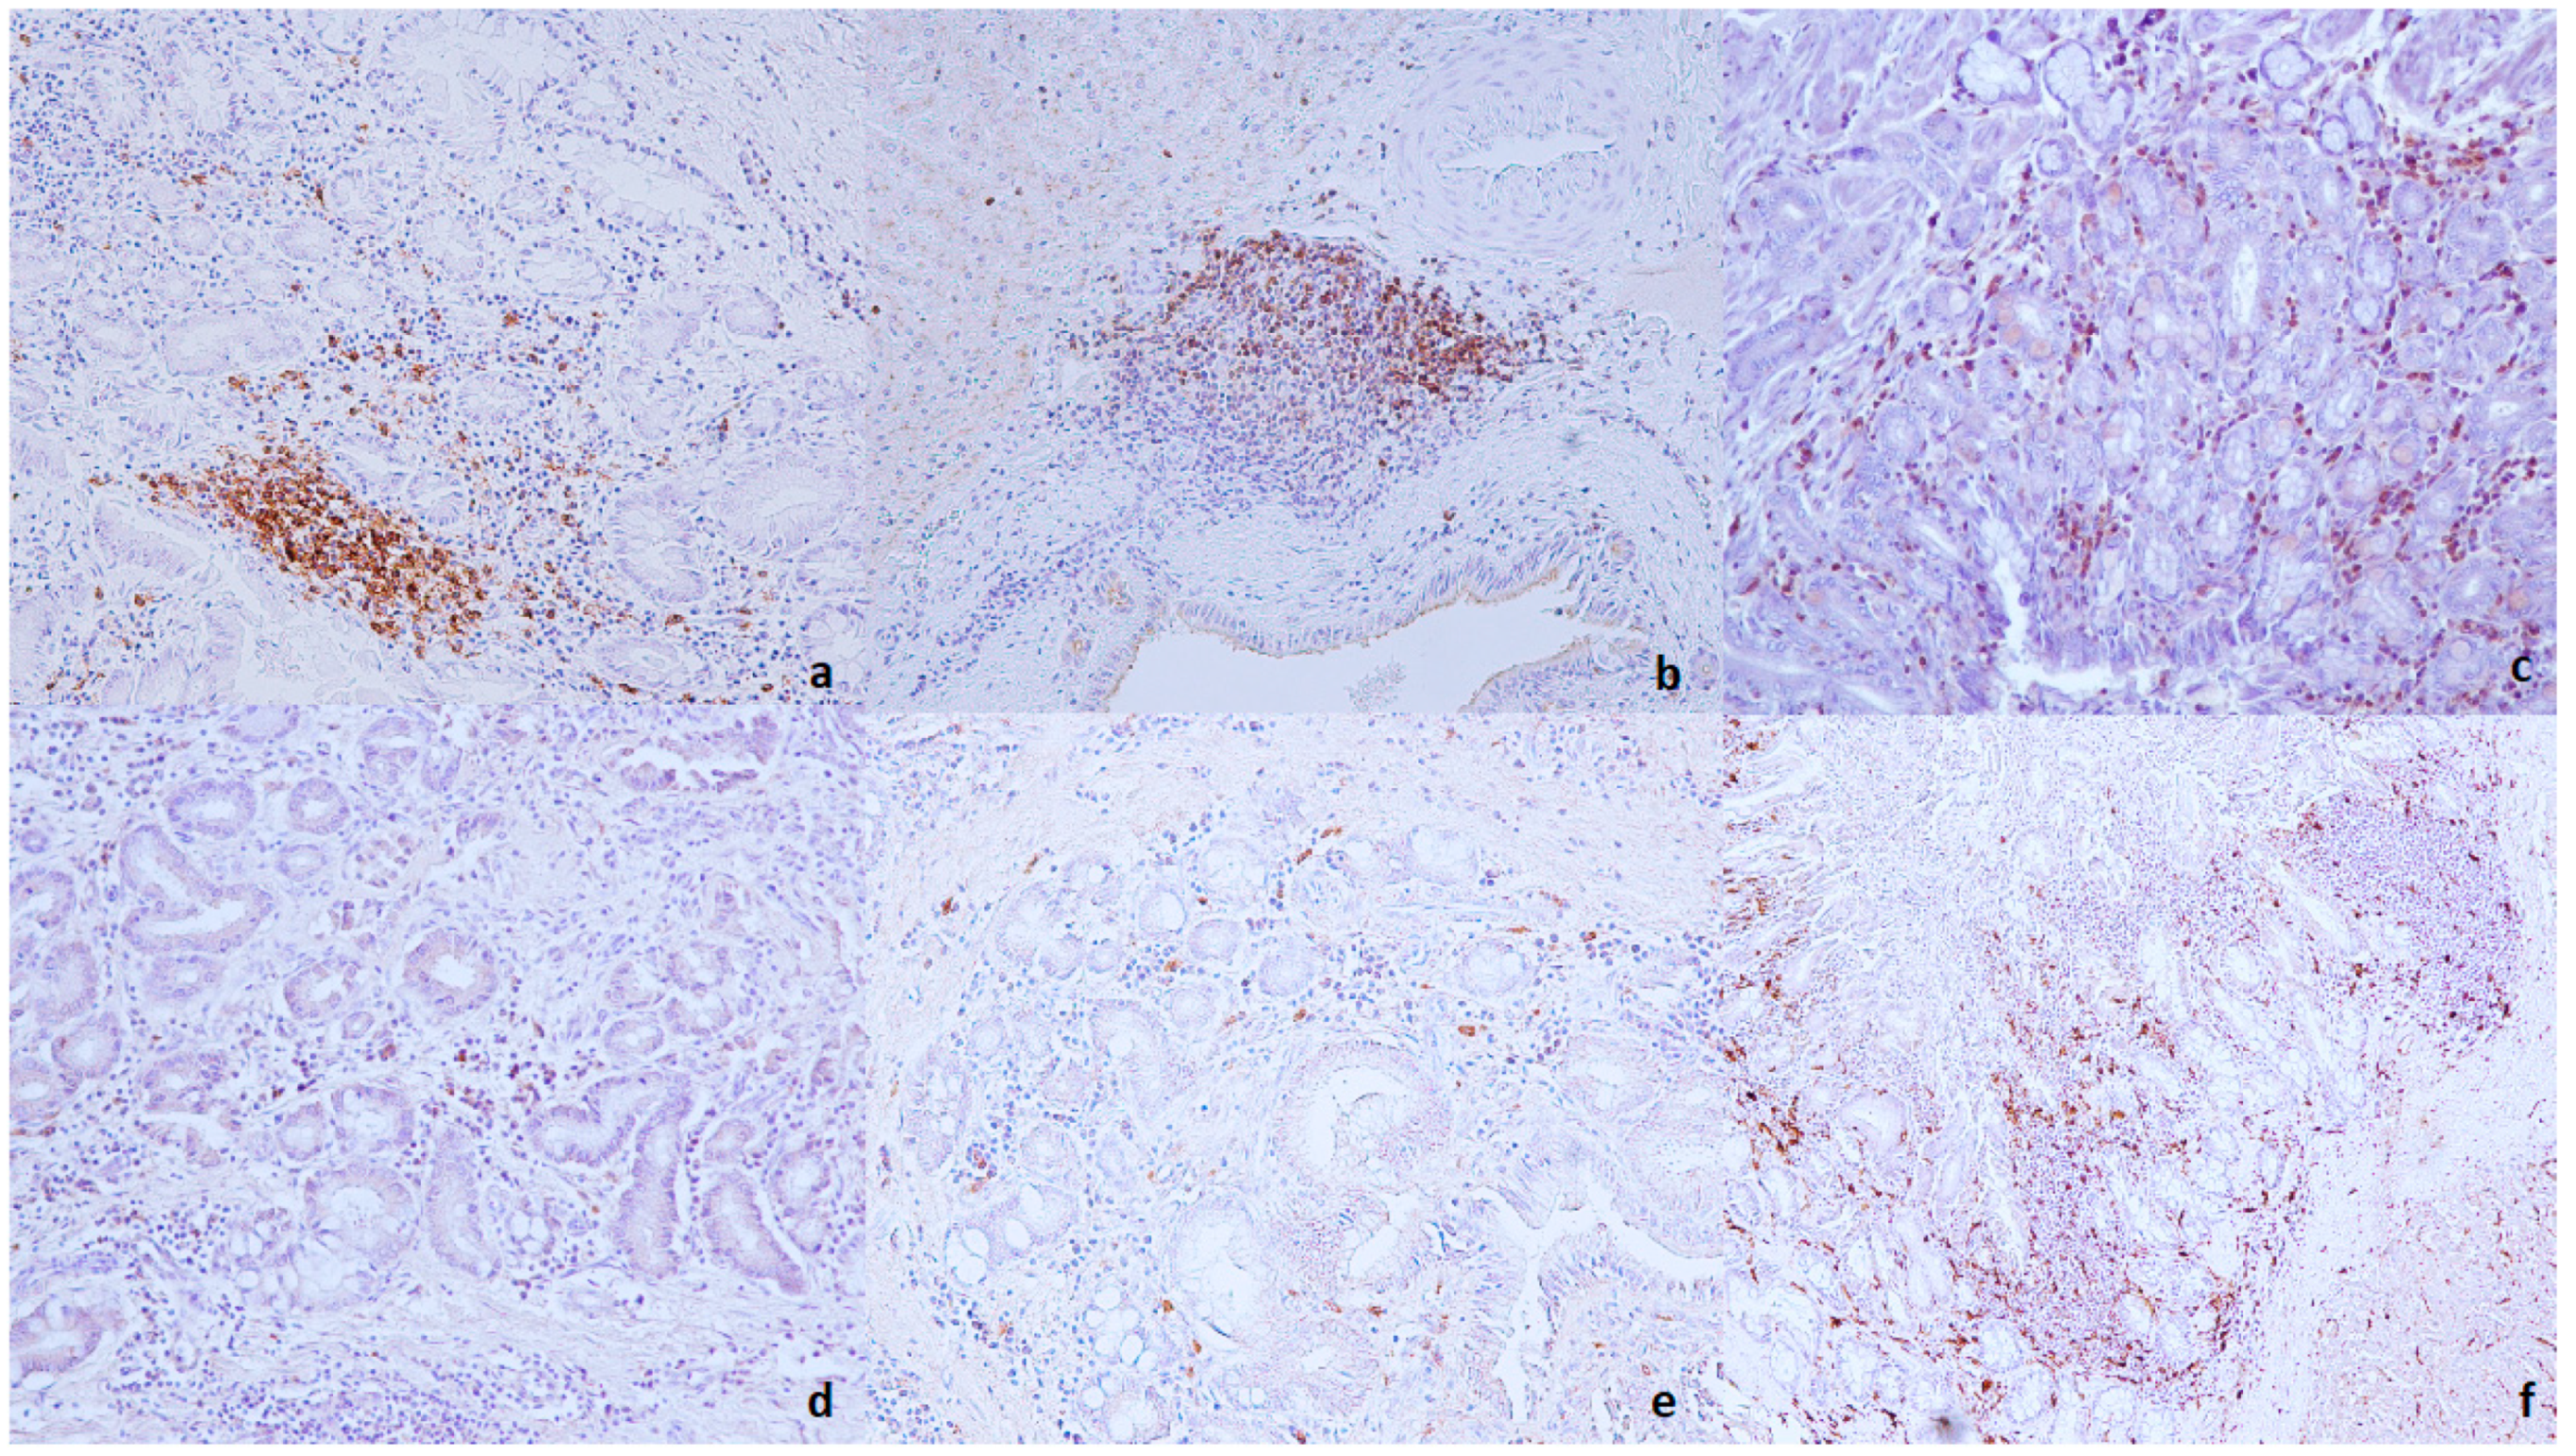

3.4. Immunohistochemical Evaluation

4.3. Immunohistochemical Evaluation